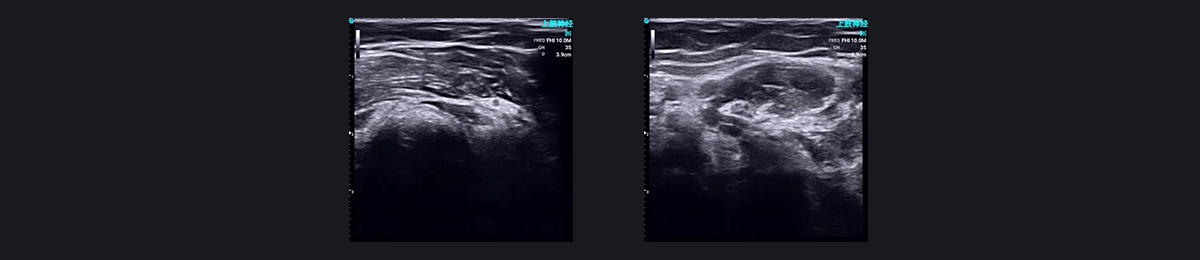

SonoEye 演示图像:神经阻滞麻醉

高频超声可以清晰地显示周围神经,使麻醉师能够以更高的精度和更少的猜测来进行神经阻滞。

穿刺前,使用超声波观察目标神经和周围的解剖结构。手术过程中,实时超声成像跟踪针的路径,避免损伤神经和血管,并监测局麻药的扩散以确保有效分布。这种方法可以使用最小有效剂量的局部麻醉剂进行精确的神经阻滞。

周围神经卡压综合征、周围神经性疼痛、颈交感性头痛和头晕等病症可以通过超声引导的局部治疗或神经阻滞麻醉来治疗。这些技术也可用于术后疼痛管理。超声引导周围神经阻滞准确、微创、高效,得到临床广泛认可。